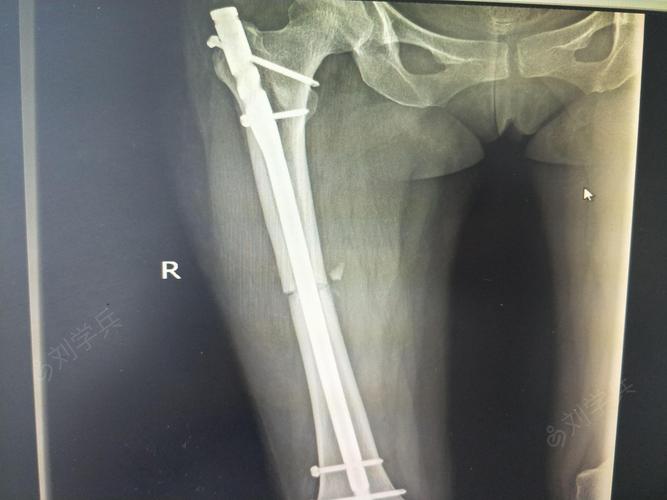

股骨干骨折位置图片

股骨干骨折位置图片,股骨干骨折骨牵引图片

股骨干骨折髓内钉图片